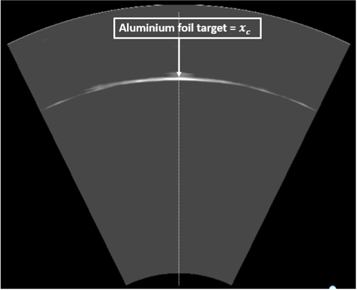

3.3.2. Bragg peak localisation in an ultrasound image

The combination of the ionoacoustic measurement with an ultrasound image requires a slightly modified calibration with regard to the calibration distance while the calibration time stays unaltered as presented in the previous section. Instead of measuring the distance to the aluminium foil target physically, the calibration location is obtained from an ultrasound image taken at the same measurement location as the optoacoustic calibration measurement. This calibration thus maps the calibration time to the location in the ultrasound image where the aluminium foil target is displayed, which is called the calibration location xc . This ultrasound image is shown in figure 12.

Figure 12. Ultrasound image of the aluminium foil target defining the calibration location xc . The ultrasound image is recorded at the same lateral position as the optoacoustic measurement used for the extraction of the calibration time tc (see figure 11).

Download figure:

Standard image High-resolution imageFor the calibration process neither the absolute distance to the Aluminium foil target nor the speed of sound of the water matters since they are equal for both devices given that both devices measure on the beam axis. A higher or lower speed of sound of the water changes the arrival time of the optoacoustic signal but simultaneously stretches or compresses the ultrasound image since the ultrasound probe assumes a constant speed of sound of vUS = 1.54 mm μs−1 for image generation. It has to be assumed that the dispersion in the frequency range between the acoustic signals (80 kHz) and the ultrasound probe (3.5 MHz) is negligible, which has been shown for water and haemoglobin solutions mimicking soft tissues (Treeby et al 2011).